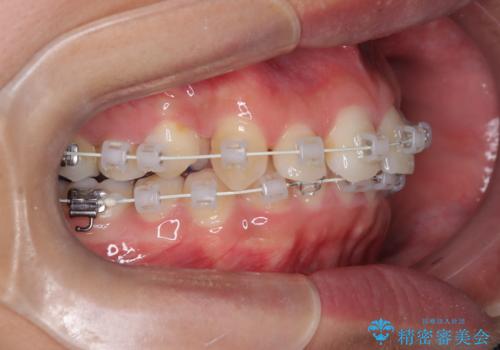

- 矯正装置

- ワイヤー(審美装置)

叢生(歯のデコボコ)の量が多く、加えてディープバイト(過蓋咬合)や重度の捻転も認められたため、リンガルアーチやマイクロインプラントなどの補助装置を併用し、治療を進めました。

治療途中では咬み合わせの改善を目的としてバイトアップを行い、歯の捻転や叢生を改善しつつ、機能的に安定した咬合を獲得しています。